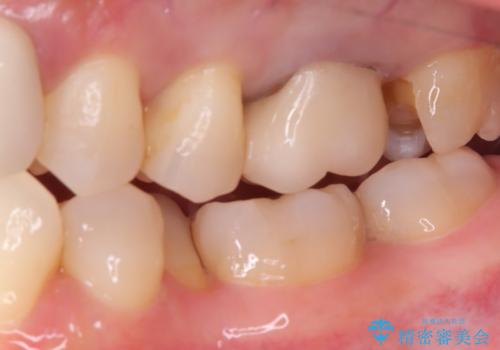

- 主訴:昔入れた銀の詰め物を白い物に替えて金属を無くしたい。

審美性、適合性の観点からセラミックインレーでのやり替えとなりました。

保険適用のメタルインレーを除去した際、下に広がっているカリエスも除去し形成印象を行いました。

セラミックインレーセット時はラバーダム防湿を行っています。